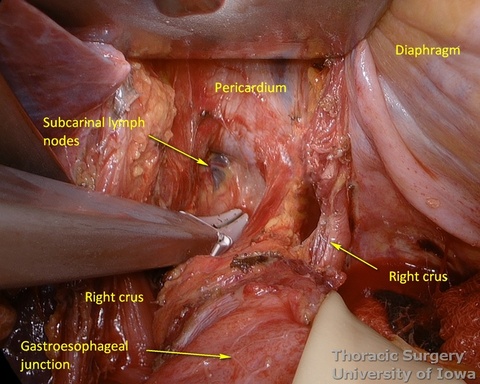

- The mediastinum is entered with the combination of sharp and blunt dissection. Note that postradiation adhesions become denser 4-6 weeks after neoadjuvant treatment.

- Once the mediastinum entered, the manual palpation through the hiatus is performed to assess mobility of the esophagus. Tumor is “rocked” from side to side to make sure it is not adherent to the aorta, prevertebral fascia, or mediastinal structures, thus assuring the feasibility of transhiatal approach or the need to perform transthoracic dissection. This should also be planned based on preoperative imaging.

- The illuminated transhiatal retractor is advanced into posterior mediastinum under direct vision

- The distal thoracic esophagus is visualized.

- Esophagus is circumferentially mobilized under direct vision using combination of sharp and blunt dissection up to the level of the carina.

- Esophageal arteries (aorto-esophageal branches) and vagal nerves are divided under direct vision using the energy device.

- Periesophageal and subcarinal lymph nodes are dissected separately or en-block with the esophagus under direct vision.

- Use of energy devices should be limited near the membranous portions of the airways.

- Dissection of the distal and mid esophagus is completed using a combination of an energy device and suction tips.